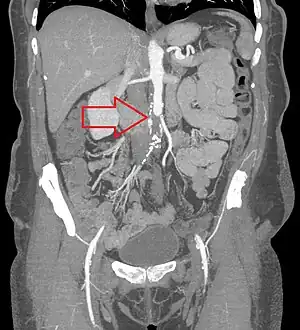

| CT angiogram showing a complete blockage or the aorta (red arrow) with the lower limbs supplied by collaterals | |